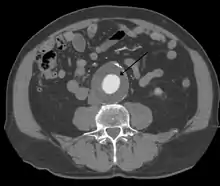

The diagnosis of an abdominal aortic aneurysm can be confirmed by the use of ultrasound. Rupture may be indicated by the presence of free fluid in the abdomen. A contrast-enhanced abdominal CT scan is the best test to diagnose an AAA and guide treatment options.[10]

The risk of rupture of an AAA is related to its diameter; once the aneurysm reaches about 5 cm, the yearly risk of rupture may exceed the risks of surgical repair for an average-risk patient. Rupture risk is also related to shape; so-called "fusiform" (long) aneurysms are considered less rupture-prone than "saccular" (shorter, bulbous) aneurysms, the latter having more wall tension in a particular location in the aneurysm wall.[9]

Before rupture, an AAA may present as a large, pulsatile mass above the umbilicus. A bruit may be heard from the turbulent flow in the aneurysm. Rupture may be the first sign of AAA. Once an aneurysm has ruptured, it presents with classic symptoms of abdominal pain which is severe, constant, and radiating to the back.[9]